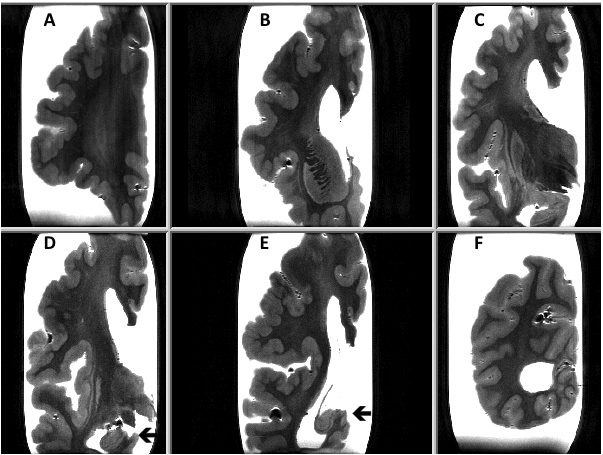

We present a post-mortem 7.0-Tesla magnetic resonance imaging (MRI) study of a 70-year old man with a history of epilepsy, due to PMG and suspected hippocampal sclerosis. Six coronal sections of a cerebral hemisphere and a horizontal section of a cerebellar hemisphere were examined with T2 and T2* sequences. PMG was mainly observed in the parietal cortex. The hippocampus had a normal aspect. Moderate white matter changes (WMC) were present mainly in the parietal region. No cortical micro-infarcts were observed (Figure 1). On the T2* sequence only a few cortical micro-bleeds (CoMBs) were present. The cerebellar cortex had a normal appearance.

Figure 1 On the T2 MRI sequence polymicrogyria is mainly observed in the parietical cortex (sections D and F). The hippocampus has a normal appearance (arrows).

This is the first post-mortem study 7.0-tesla MRI study of PMG that confirms the validity of the “in vivo” imaging. The present case shows mainly parietal gyral malformations. The WMC and CoMBs are to be considered as age-related changes, as observed in normal elderly brains.5